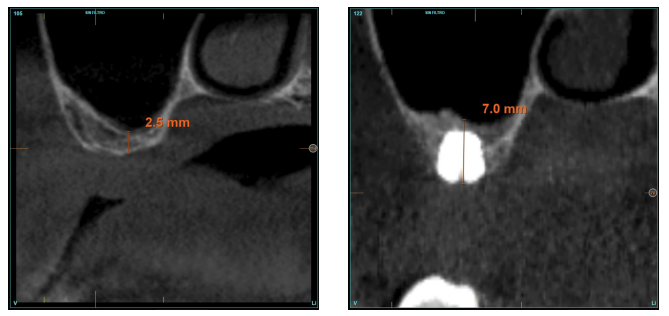

La altura media del volumen óseo residual fue de 3,1 mm (+/- 0,3 mm con un rango de 3-4 mm). En todos los casos se realizó una elevación de seno transcrestal, con hueso autólogo particulado obtenido del fresado de la zona de generación del neoalveolo para la inserción del implante, siendo la media de esta elevación sobre el ápice del implante en milímetros de 2,8 mm (+/- 0,99 rango 1,9 -5 mm). En el TAC de control al año de carga de los implantes estudiados, se mantiene la ganancia ósea lograda, no observándose disminución del volumen ganado, únicamente tres casos mostraron una disminución de entre 0,4 y 0,5 mm del volumen inicial al final (Tabla).

En las Figuras 2- 19 se muestra uno de los casos incluidos en el estudio.

la oseointegración del implante 6 meses después de la cirugía. Se observa una ganancia ósea de 4 mm.

implante y el volumen óseo ganado y conservado tras la función de los implantes.